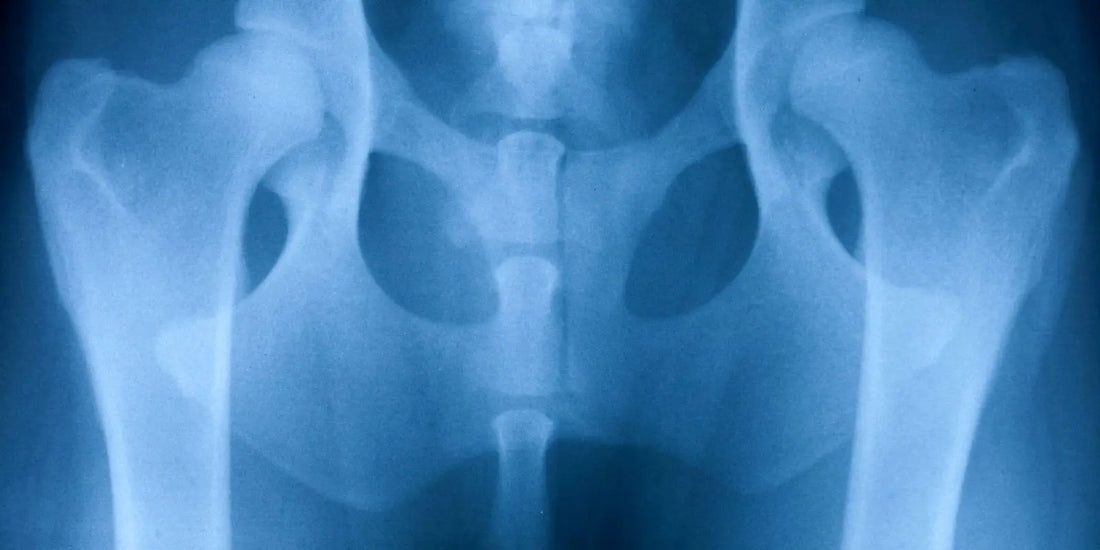

🔹 Chez le chat , l'arthrose apparaît souvent après 10 ans . Cependant, des études montrent que plus de 60 % des chats de plus de 6 ans présentent des signes d'arthrose à la radiographie, même sans symptômes visibles. Près de 90 % des chats de plus de 12 ans présentent des lésions arthrosiques , et 45 % montrent des signes cliniques visibles .

✔ Dysplasie (hanches, coudes), malformation articulaire